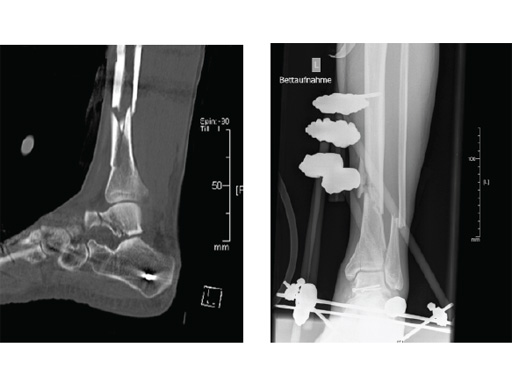

Case provided by Gerhard Schmidmaier, Heidelberg, Germany

Clinical example of the first patient treated with the new ETN PROtect.

Case 1: A 33-year-old man with a third degree open fracture of his left tibia was initially treated with an external fixator and unilateral compartment release. He had undergone ACL reconstruction in the past.